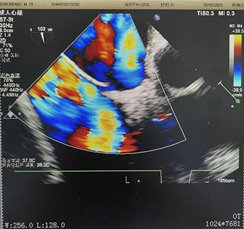

于是对患者进一步行经胸常规二维超声心动图检查,但未见明显异常。是否因异常分流通道面积太小,常规心脏超声检查不能发现?于是进一步行经食道超声心动图检查,果然发现位于房间隔中部有一宽约2.0mm的左向右斜型蓝色分流信号,提示卵圆孔未闭型房间隔缺损。

行右心声学造影可见明显右向左分流,TCD发泡试验阳性(固有型,III级,雨帘样)。